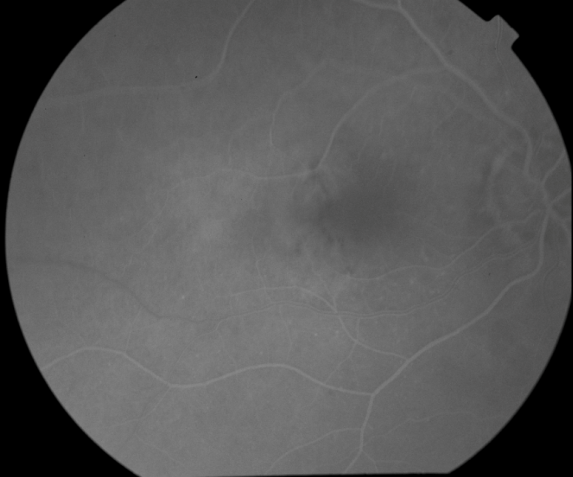

OD Red-Free: Pre-Injection: Arterial: A-V: Venous: Recirculation: Late:

OS Red-Free: Venous: Recirc: Late:

Impression